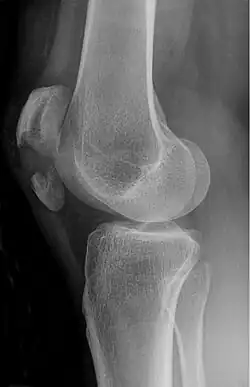

The patella can break in various ways depending on the way it is injured, and into two or more pieces.[1] Types include transverse, the most common, with one fracture line;[5] marginal; osteochondral; and the rare vertical type, or stellate, where a direct compression force gives rise to a comminuted pattern.[5][7] Patella fractures can be further classified as displaced, where the broken ends of bone do not line up correctly and separate by more than 2mm, or undisplaced and stable where pieces of bone remain in contact with each other.[1][7] If fragments of patella bone stick out from the skin it is known as an open patella fracture, and closed if the overlying skin is intact.[1]

Transverse fracture of patella -

Comminuted fracture of patella -

Osteochondral fracture of patella -

Vertical patella fracture